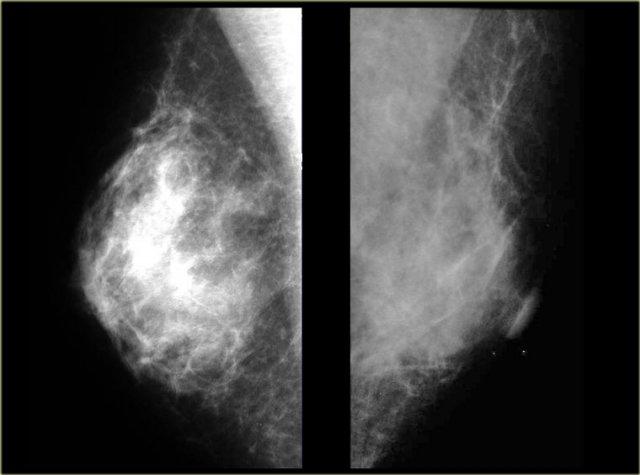

Bên trái là nhũ ảnh cho thấy vùng đậm độ dưới quầng vú với các nhánh kéo dài nổi bật vào mô mỡ.

Thông thường vùng đậm độ nhỏ hơn so với thể nốt.

Trên nhũ ảnh bên trái, chúng ta có thể hình dung có sự xơ hóa với các nhánh kéo dài vào mô mỡ.

Điều này khác với hình ảnh phù nề tuyến trong giai đoạn cấp tính của gynecomastia.

Siêu âm cho thấy hình ảnh có gai.

Các trường hợp này minh họa rõ ràng rằng gynecomastia có thể có hình ảnh mà chúng ta sẽ gọi là ác tính ở phụ nữ.